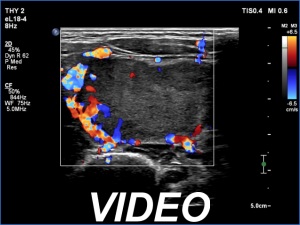

Second examination - five years later (second row of images)

Clinical presentation: The patient came to follow-up because she noticed a slow increase in the size of the left lobe.

Palpation: a firm nodule in the left lobe.

Laboratory tests: TSH 0.98 mIU/L.

The dimensions of the nodule in the left lobe were 40x25x43 mm, width, depth, length, respectively, the volume of the lesion was 22.5 mL.

Aspiration cytology resulted in follicular tumor. Surgery was advised.